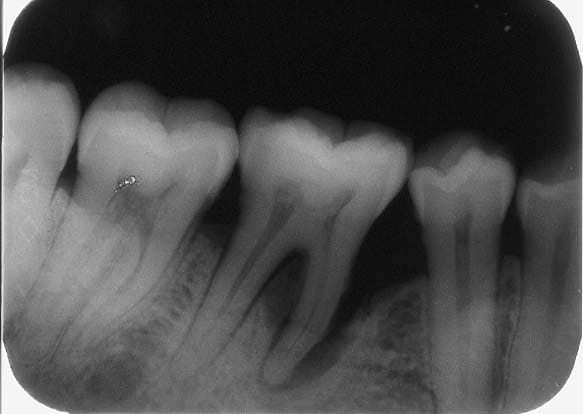

Ai reçu radios d'un cas similaire de Rogé.... dent traitée par UNIQUEMENT un meulage selectif.... si il veut bien réadresser les images (et si il a images + récentes avec évolution....). C'est assez instructif.

Suite à la demande de Algi, voir le cas suivant:

historique du cas :

Patiente venue en consultation le 19/12/03 .........*douleur et abcé

parodontal sur la 46......poche purulente et grande mobilité verticale

et horizontale.

*presciption d antibiotique + anti inflamatoir........2 detartrages +

equilibration occlusale sur 3 seances........disparition de douleur dès

la 1ere seance.

meulage de la 46 en contact prematurée importante.

A la 3e seance.......disparition des douleurs et de l abcé..............

/voir radio qui montre une destruction importante du septum intra

radiculaire et du septum mesial + une resorption tres importante de la

racine mesiale.

/7 mois après........visite de controle et radio ci joint. Tres agreable

surprise.

*On constate une regeneration de l os alveolaire ds le septum

intraradiculaire et un peu du coté mesiale.*

Visible à fort grossissement.........x 200 %

Disparition totale de la mobilté dentaire........mm solidité que la 37.